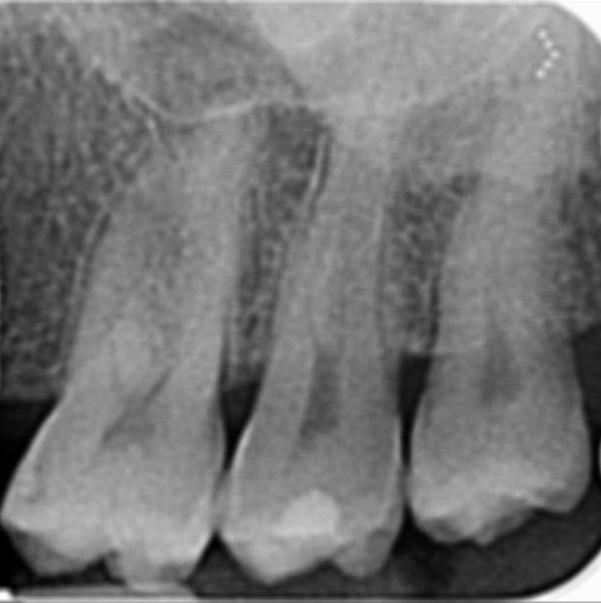

Salve.Io da un bel po di mesi ho continui dolori in zona molari superiori a sinistra.Ho effettuato almeno 20 visite dentistiche e 6 igienisti diversi mi hanno effettuato la detartrasi negli ultimi 2 anni.In una visita a Napoli un dottore mi ha fatto una rx endorale digitata ingrandita al pc e mi ha detto che tra questi 2 molari c’era tartaro calcificato da almeno 12 anni e mi ha inserito nel preventivo una carie sul secondo molare ma io tramite specchietto noto un buco nero anche sul dente del giudizio , inoltre mi ha detto che non e’ stata curata bene la carie sul premolare inferiore..Ho due carie anche se non e’ normale dopo tutte queste visite e detartrasi..Il radiologo mi ha inserito come referto questo : Piccole trasparenze smaltee interprossimali contrapposte 17-18 come per minute carie, reperti da accertare clinicamente.

Carie

sembra improbabile che i dolori di cui lei soffre siano riferibili alla parte superiore……il tartaro calcificato per esempio io non lo vedo, ne vedo particolari carie anche se devo fare i conti con una definizione non proprio ottimale delle immagine che mi ha mandato. Sinceramente proverei a riparare innanzitutto la vecchia otturazione che ha nell’arcata sottostante. Alle volte i dolori possono essere riferiti alle aree più impensate e poi rivalutarei la faccenda. Inoltre è anche probabile che quel dente la cui otturazione sarà da rifare, abbia un problema alla polpa infatti quella carie è molto profonda……. si faccia fare magari anche un test di vitalità per capire se ha bisogno di eseguire una cura canalare.

In sostanza prima di fare qualsiasi cosa nella parte superiore io agirei sotto.